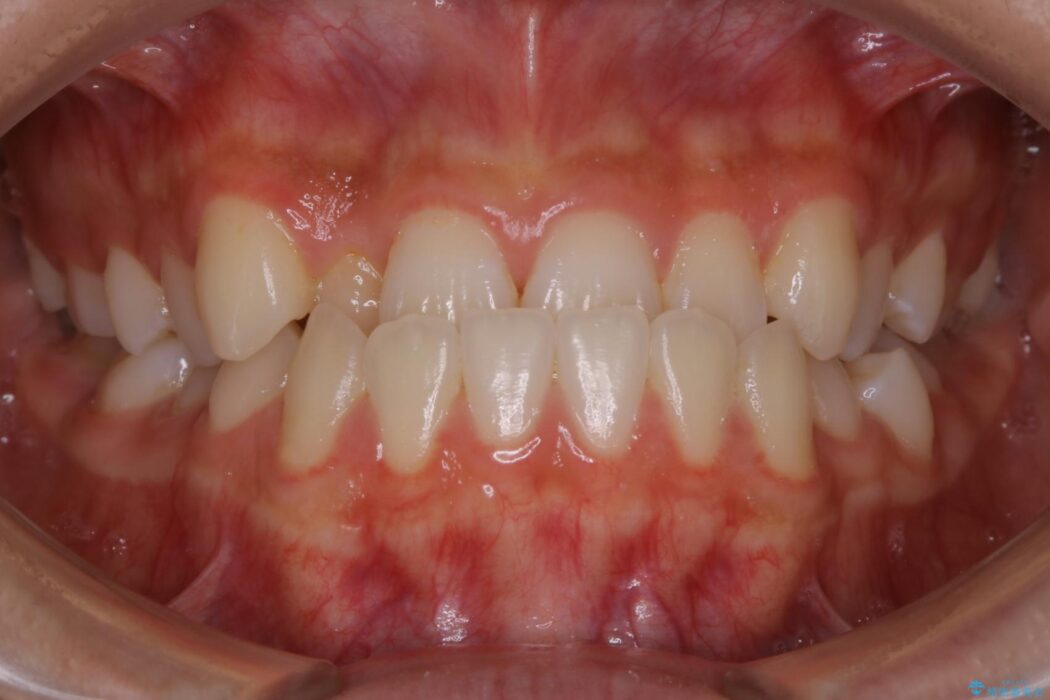

治療後について

正常な噛み合わせ位置へと改善したことにより奥歯で噛みしめることができ、加えて見た目も受け口から変わって大変ご満足いただけました。